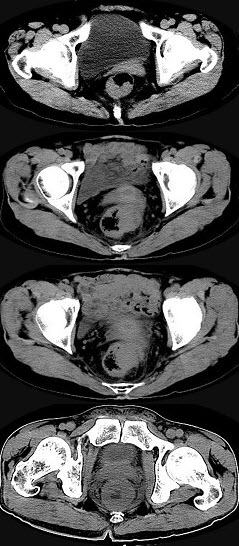

男,56岁,排便形状改变,便不尽感,CT检查如图所示,下列说法正确的是( )

A:肠壁上有蒂状新生物

B:其表面光滑,边界清楚

C:肠腔未见狭窄

D:此为直肠息肉

E:此为直肠癌